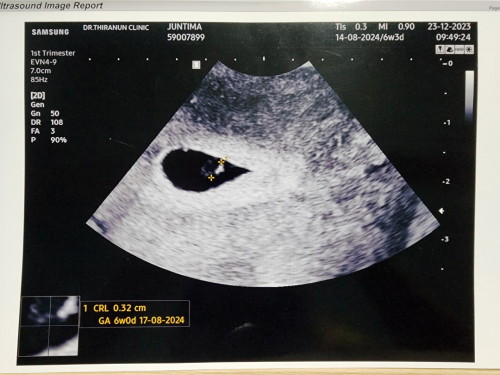

แม่เจอ6w3dค่ะ